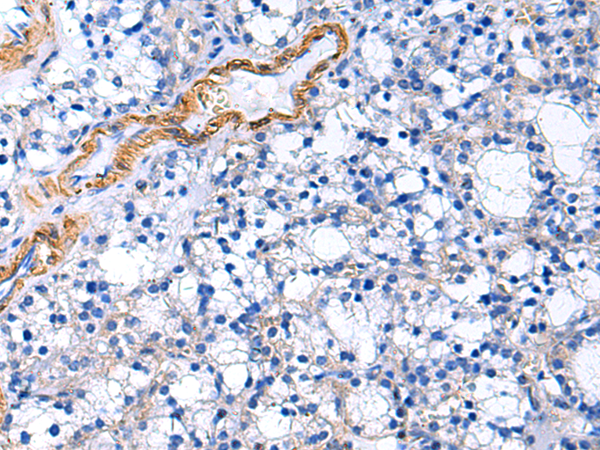

分类: 科研抗体货号: P06441别名: PC; APC; PROC1; THPH3; THPH4应用: WB,IHC反应种属: Human